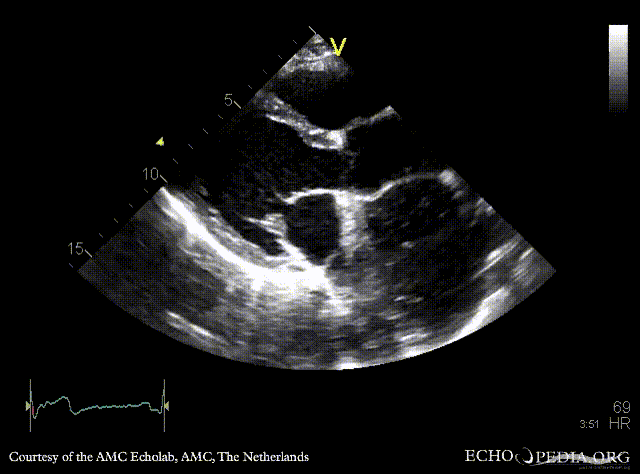

| PLAX: large cyst adjacent to left atrium, compression of LA | PSAX |